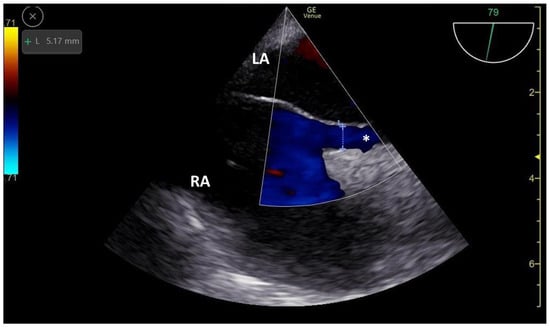

3.1. TCCD MES-Positive Case 1

3.2. TCCD MES-Positive Case 2

3.3. TCCD MES-Positive Case 3